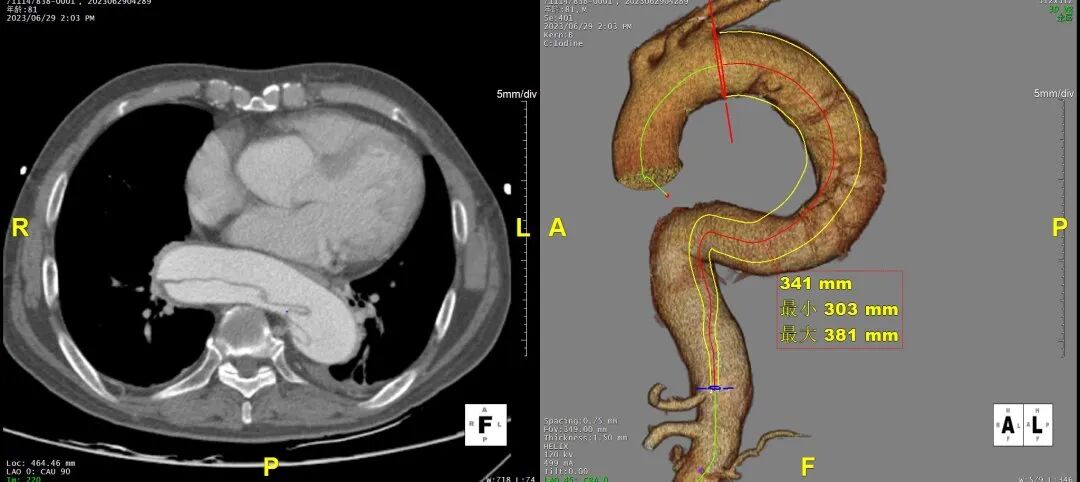

术后随访

术后随访复查,支架形态良好,真腔重塑良好,四分支及下肢血供良好。

横断面影像

3D影像